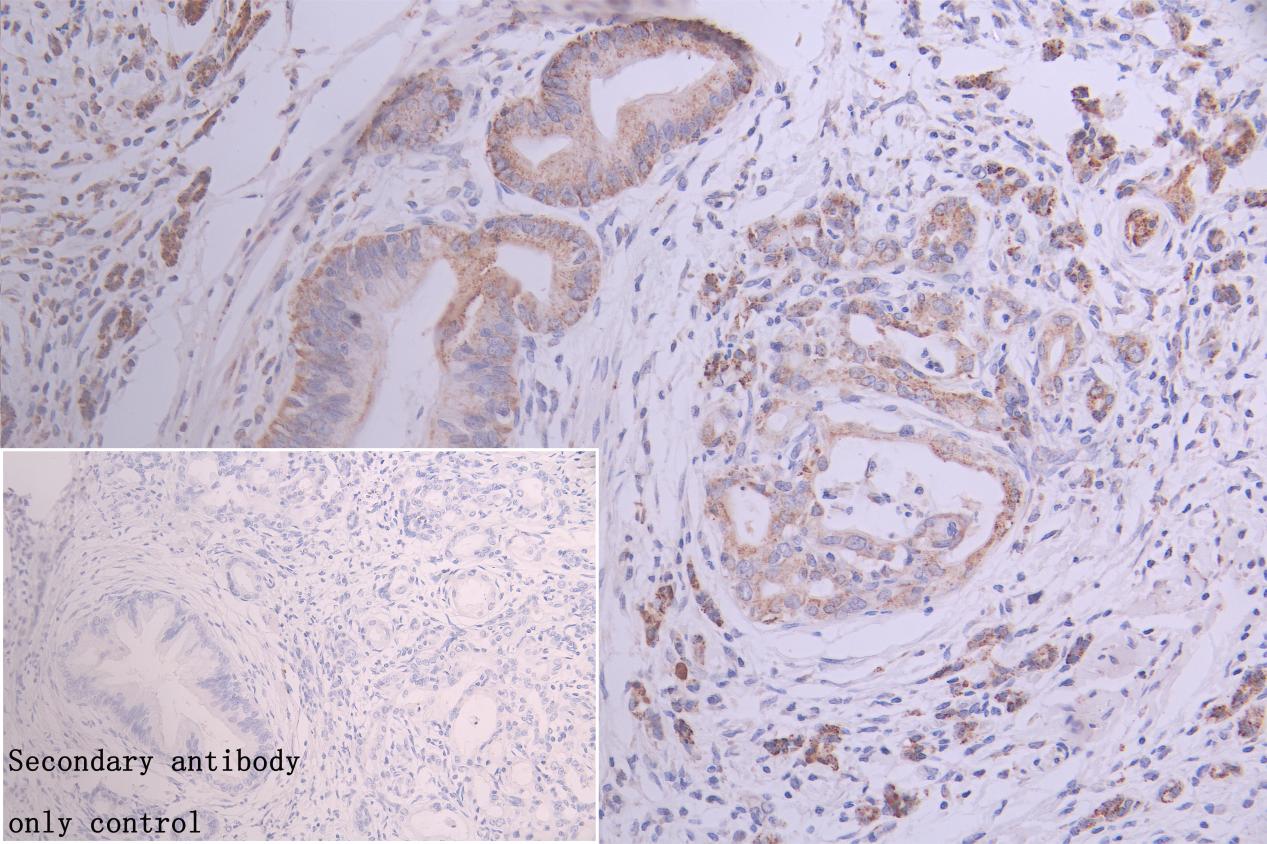

IHC image of CSB-PA009284ESR1HU diluted at 1:300 and staining in paraffin-embedded human pancreatic cancer performed on a Leica BondTM system. After dewaxing and hydration, antigen retrieval was mediated by high pressure in a citrate buffer (pH 6.0). Section was blocked with 10% normal goat serum 30min at RT. Then primary antibody (1% BSA) was incubated at 4°C overnight. The primary is detected by a Goat anti-rabbit polymer IgG labeled by HRP and visualized using 0.05% DAB. Secondary antibody only control: uses 1% BSA instead of primary antibody